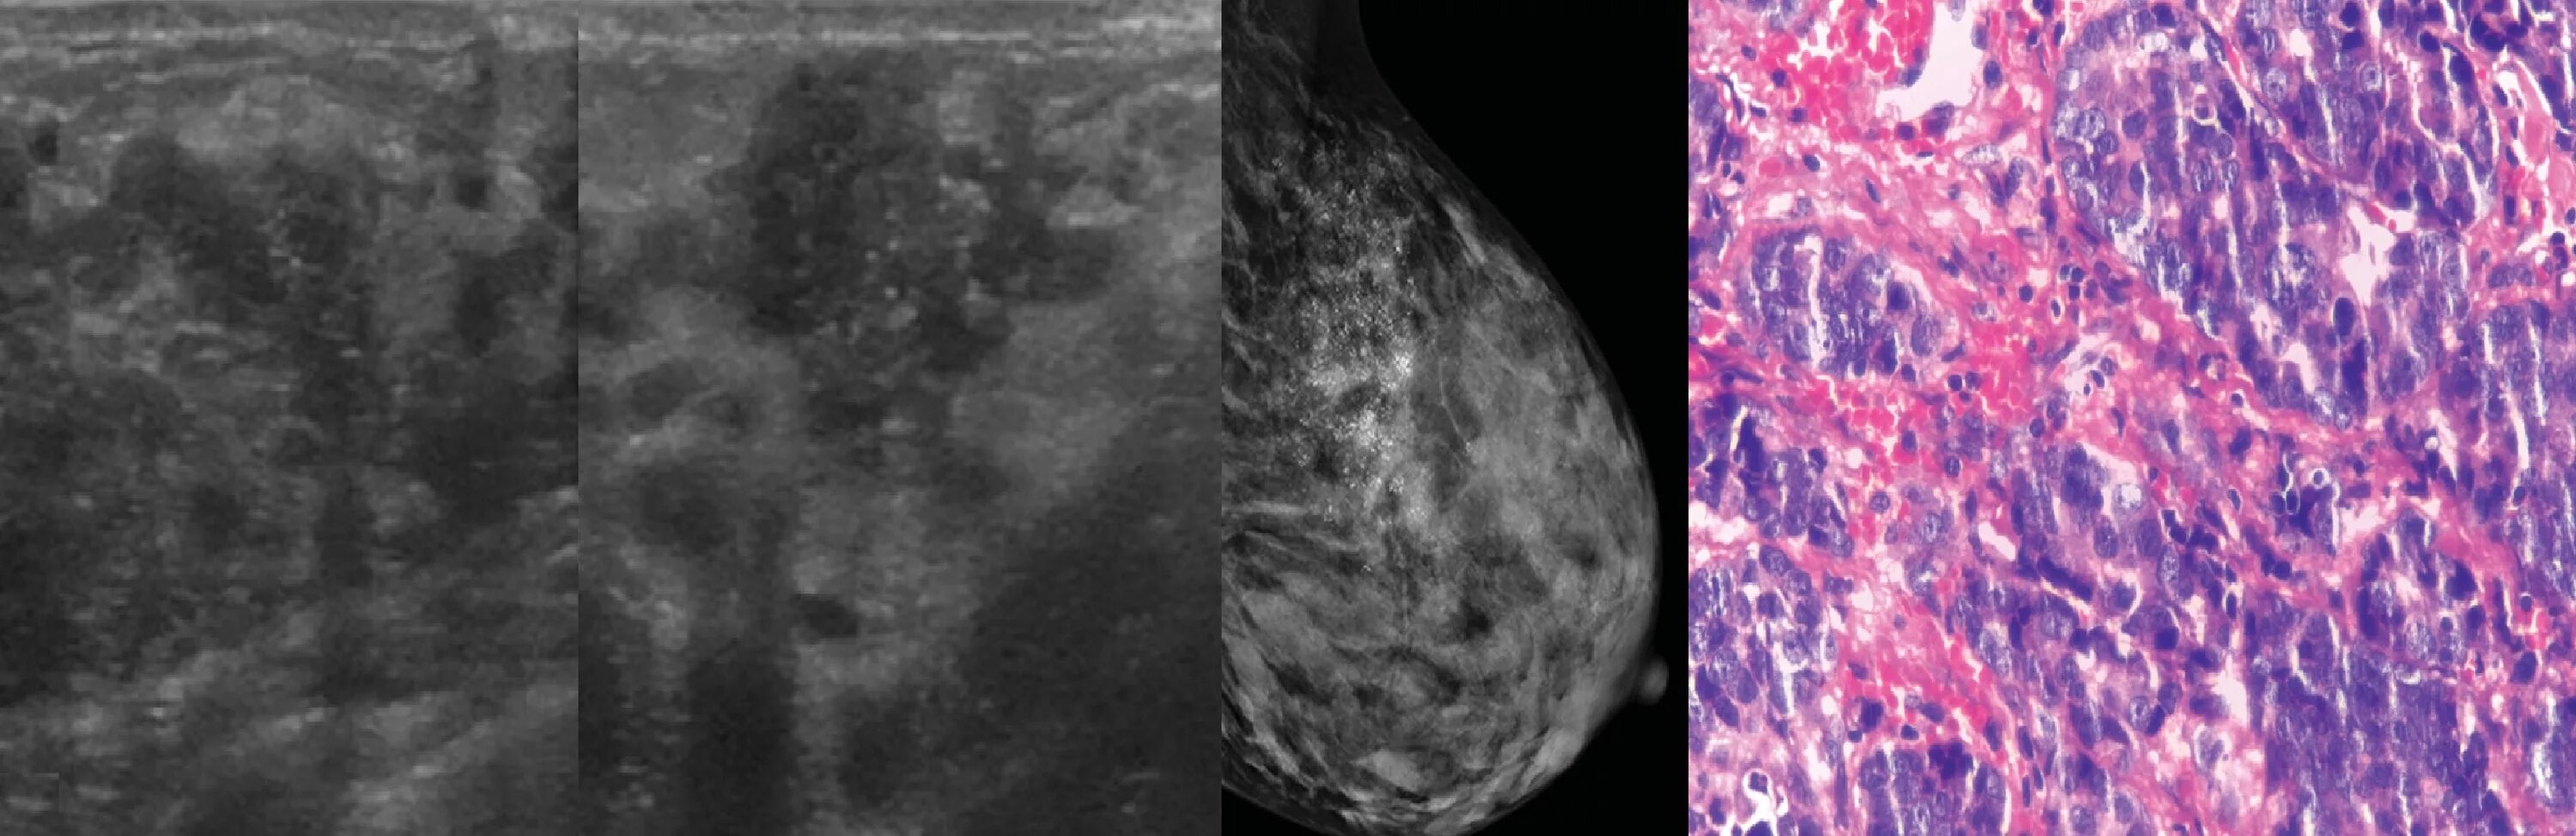

Диффузные фиброзные изменения молочной железы